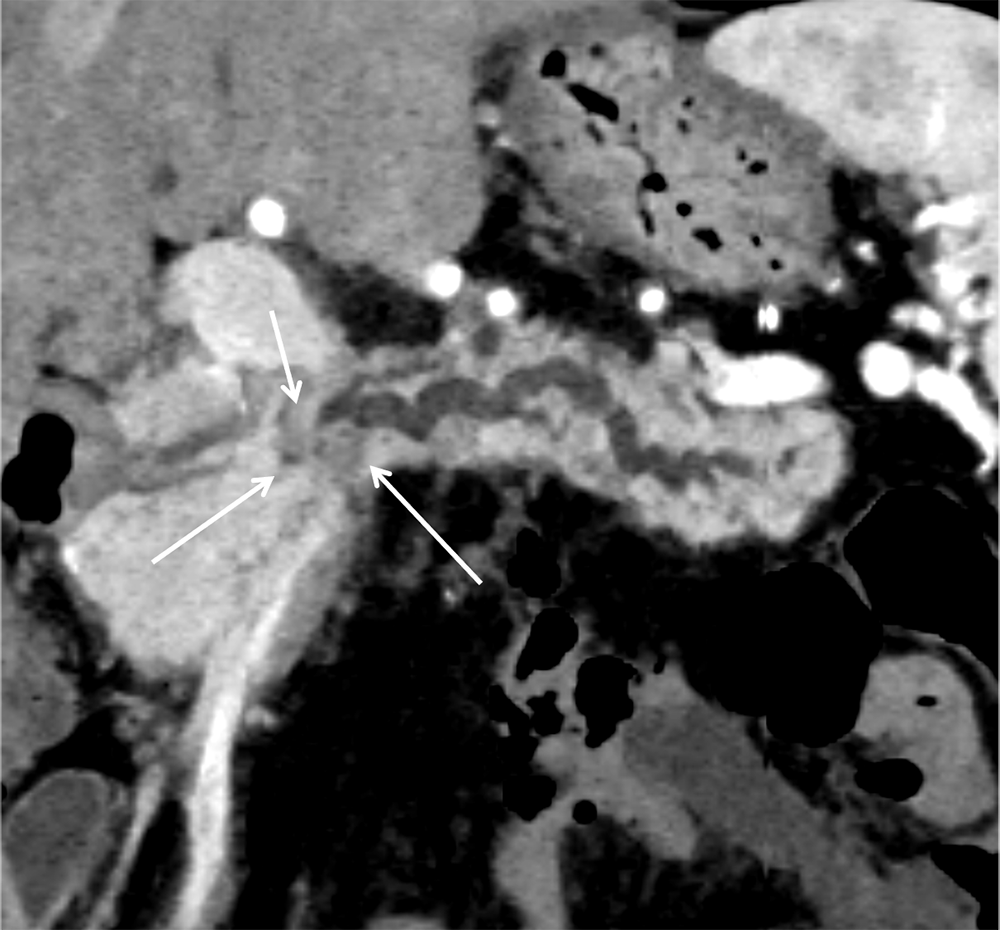

さらにthinスライスのCT画像、MPR(multi-planar reconstruction)、Dual-energy CTを用いた低エネルギーレベルの仮想単色X線画像やIodine mapの併用で、検出能向上や病期診断の精度向上につながると考えられる。Iodine mapは、Dual energy CTのデータからヨード造影剤を抽出して画像化したもので、ヨード濃度とその分布を把握することができる。本症例でも、Iodine mapでは病変と周囲膵実質のヨード濃度の差がわかりやすく、病変をより認識しやすくなった。また、MPR像を用いることで、通常の水平断面像と比べて、病変と主膵管との位置関係の把握が容易となった。